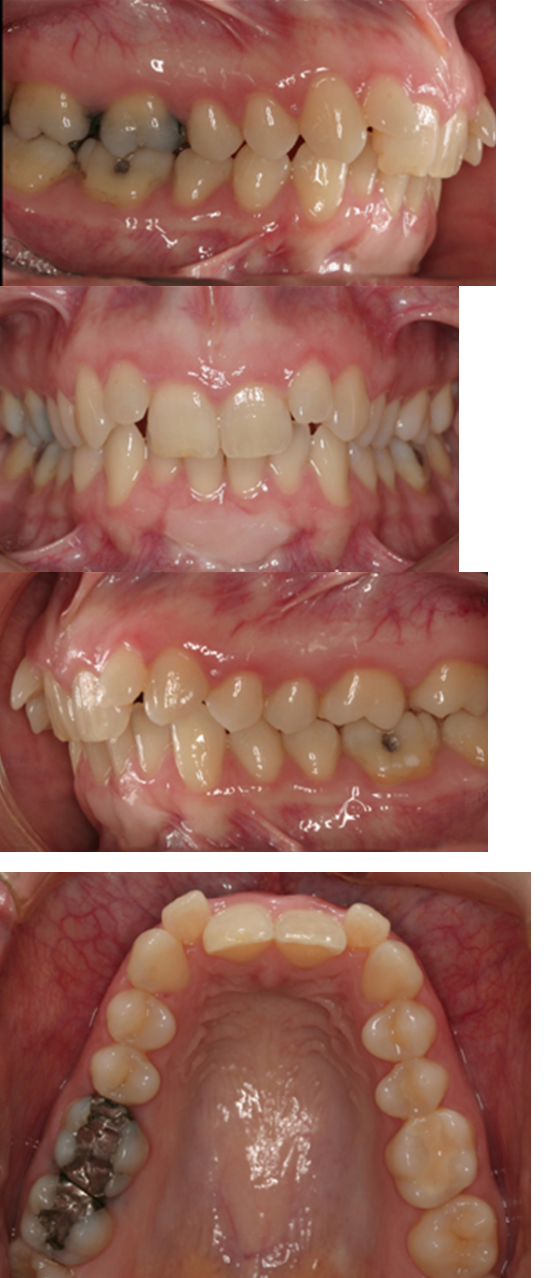

class II division 1

What is the Angle's classification for this patient?

class II division 1 subdivision right

class II division 2

class III

convex

This patient's profile is: